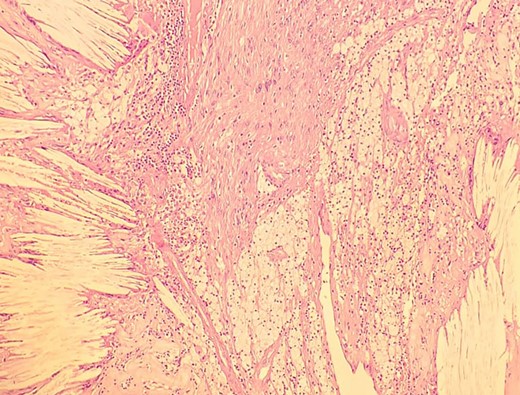

A man in his 30s presented with symptoms suggestive of irritable bowel symptoms with increased bowel movements coinciding with the onset of colicky abdominal pain for the past 8 months. The bowel movements relived his pain and had no remission from his symptoms. He had no relevant medical comorbidities in the past. The patient had normal vitals. There were no physical exam abnormalities except for a slight fullness in the left renal angle (Fig. 1). There was nothing significant on a rectal examination. An X-ray of the chest showed normal findings. Blood investigations showed: haemoglobin 130 g/l, total leukocyte: 7.4 × 109/l, serum creatinine 0.52 mg/dl, fasting blood sugar 90 g/dl, alanine transaminase 26 U/L, aspartate transaminase 42 U/L, alkaline phosphatase 32 U/L and total bilirubin 0.8 mg/dL. Ultrasonography showed a 10-cm mass, with mixed echogenicity. Posterior to the left kidney. Colonoscopy was normal. An abdominal CT scan showed a paravertebral tumour with peripheral enhancement and heterogenous contrast within the tumour (Fig. 2). The tumour showed high intensity on a T2-weighted MRI (Fig. 3). The left kidney and colon were displaced anteriorly. Fine-needle aspiration biopsy was inconclusive. The clinical diagnosis was a retroperitoneal schwannoma. On laparotomy, the left colic vessels appeared to be splayed by the tumour (Fig. 4). The tumour 11 × 6 × 3 cm3 (Fig. 5), which seems to be arising from the L2 nerve, was resected completely (Fig. 6). The patient had no sensory or motor loss postoperatively. He was discharged without complications on the 10th postoperative day. His colonic symptoms had disappeared after surgery. The gross appearance of the resected tumour showed cysts and haemorrhage patches (Fig. 7). Histopathology showed areas of hypercellularity (Antony A) and hypocellularity (Antony B) with degenerative changes leading to nuclear atypia and cystic spaces, typical of an ancient schwannoma (Figs 8–11). Immunohistochemistry with S-100 was positive (Fig. 12). He was devoid of digestive symptoms or radiological evidence of recurrence at 12 months.

Low-resolution 200x H&E histopathology image of the tumour showing hypercellular (Antony A) areas.

Low-resolution 200x H&E histopathology image of the tumour showing hypocellular (Antony B) areas.

High-resolution 400x H&E histopathology image of the tumour showing nuclear atypia suggestive of ancient schwannoma.

Low-resolution 200x H&E histopathology of the tumour showing foamy macrophages and cholesterol clefts suggestive of degenerative changes, suggestive of ancient schwannoma.